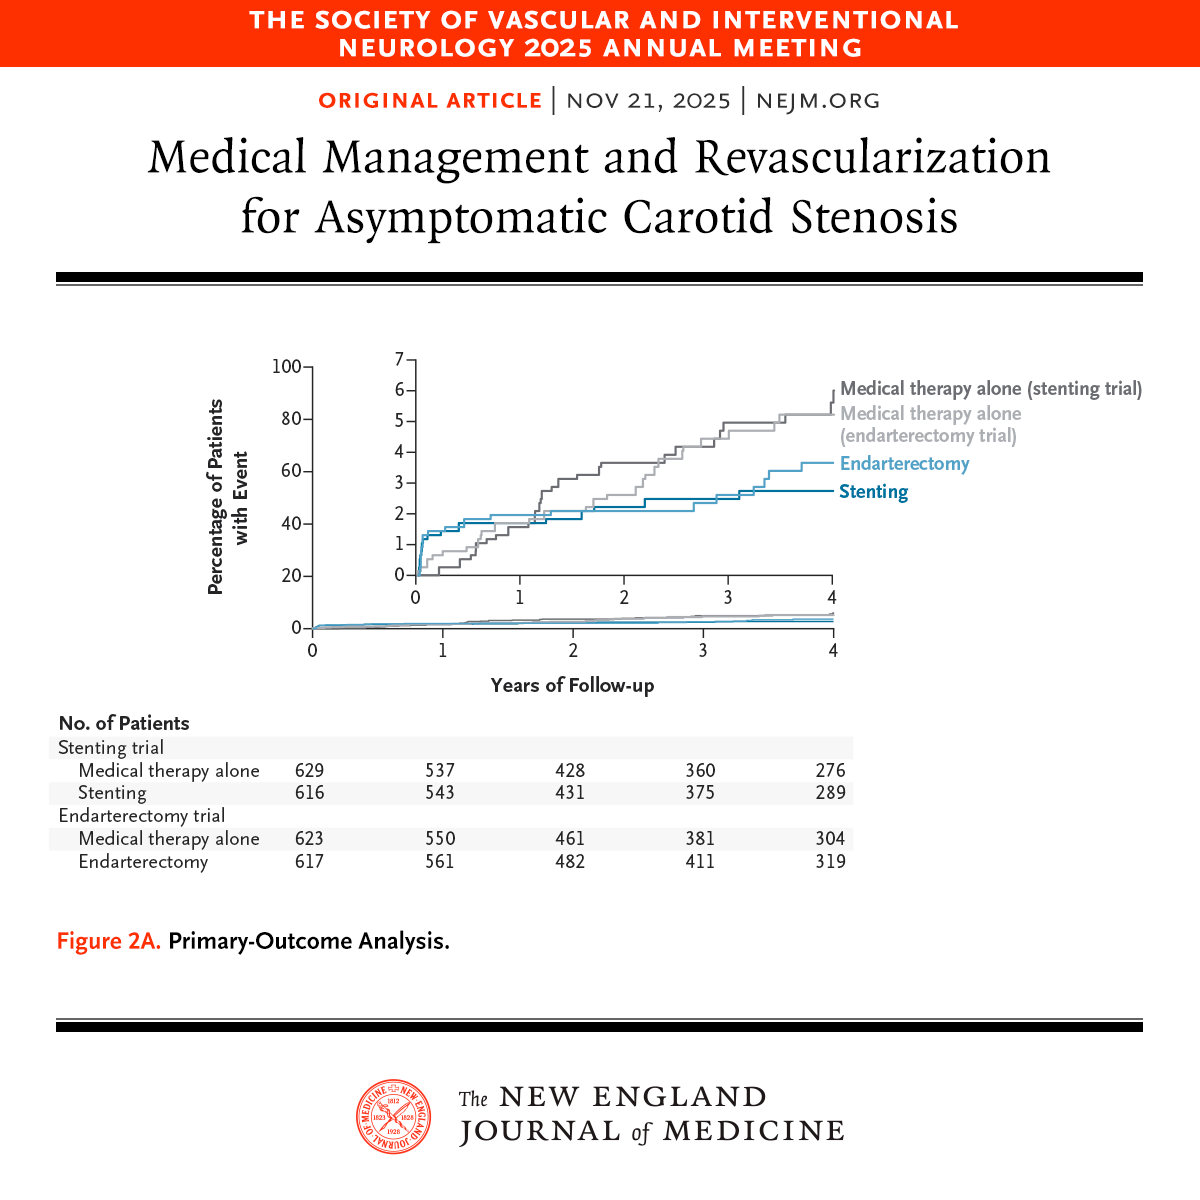

🗓️ 23/11/2025 ✅ Repasamos en 3TuitX #LaSemanaenCardioX‼️ 💚 Abrimos mini🧵 y pregunta #CardioEd 🤔 Trat médico óptimo vs endarterectomia vs stent en estenosis carotidea ⁉️ ✅ CREST-2 🔝 Beneficio trat médico óptimo + stent en estenosis carotidea

Presented at #SVIN25: CREST-2: In high-grade asymptomatic carotid stenosis, addition of stenting to medical therapy led to a lower risk of stroke over a 4-year period. Endarterectomy did not lead to a significant benefit. Full results: nej.md/3LK9kst Editorial:…